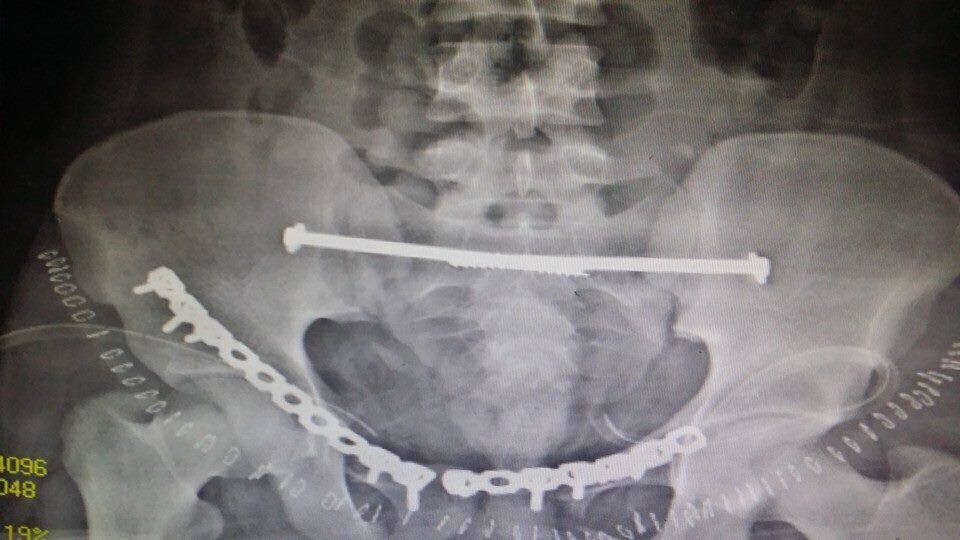

انقاذ مريض تعرض لكسور بالحوض

انقاذ مريض تعرض لكسور متعددة بالحوض

المستشفي السعودي الالماني بالرياض يواصل اجراء جراحات الحوض المعقده بنجاح لافت

يواصل المستشفي السعودي الالماني بالرياض اجراء جراحات الحوض المعقدة بنجاح كبير ، جعله من المقاصد الطبية المتميزة ،تعد جراحات الحوض من الجراحات المعقده ، التى تعتبر تحديا كبيرا يواجه جراحي العظام، حيث تتطلب مجهودا كبيرا ومهارة من جراح العظام والفريق الطبى المعاون له . وتعتبر المستشفى السعودى الالمانى بالرياض احد المستشفيات الرائدة ذات السمعة الطيبه فى هذا النوع من الجراحات خاصه وفى جراحه العظام بصوره عامه.

وكان قد حضر مريض الى قسم الطوارىء بالمستشفى اثر تعرضه لحادث سياره ،وكانت حالته العامه صعبه للغايه . وعلى الفور تم عمل الإسعافات اللازمه للمريض وتم دخوله على الفور للعناية المركزه و عمل جميع الفحوصات اللازمه من اشعات عاديه وتلفزيونية ومقطعيه ، حيث تبين وجود كسور متعدده وانفتاح فى الحوض مع وجود نزيف حاد بالحوض قد يؤثر على حياه المريض . وعلى الفور تم إيقاف النزيف بواسطه فريق متكامل من أطباء الاشعه التداخليه.

وبعد استقرار الحاله العامه للمريض ، تمت مناظره الكسور الموجودة من قبل الدكتور محمد فوزي رئيس قسم العظام ، والذى قرر بإجراء تدخل جراحى لفتح وتثبيت الكسور المتعددة بالحوض بواسطه شرائح ومسامير معينه .

وبعد عمل التحاليل اللازمه ، و دخول المريض لغرفه العمليات ، حيث قام بفتح وتثبيت الكسور . وبحمد الله وتوفيقه تمت العمليات جميعها بالحوض فى جلسه واحده وبنجاح تام ومكث المريض بالمستشفى لعده ايام بعد الجراحة للاطمئنان على الحاله العامه والغيار المستمر على الجروح . وبحمد الله خرج المريض من المستشفى بحاله جيده واستمر فى المتابعة بالعياده الخارجيه بقسم العظام بالمستشفى حتى تمكن من المشى بصوره منتظمة وطبيعية .